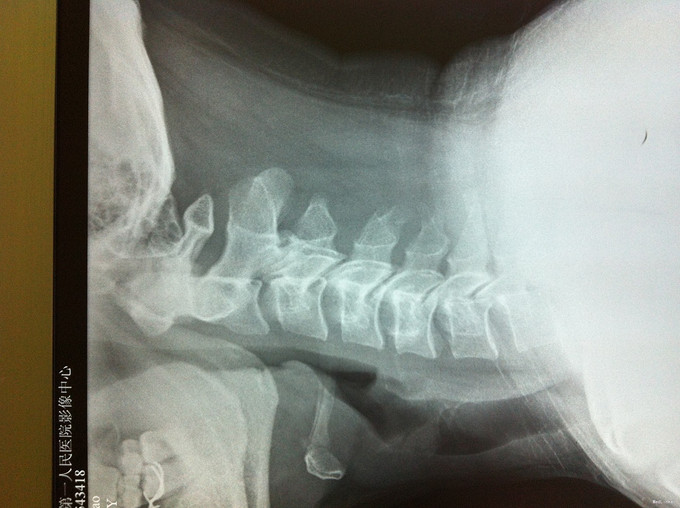

颈肩疼痛1年,加重伴左上肢疼痛、行走不稳1个月 患者1年前无明显诱因出现颈肩部疼痛不适,不伴四肢放射性疼痛、无力,劳累后加重,平卧休息可缓解。1个月前无明显诱因出现颈部疼痛加重,伴左上肢放射性疼痛,行走不稳、双足踩棉感,无高热、寒战,无低热、盗汗。

查体:左侧前臂及手感觉减退,右侧正常,左侧伸腕、伸肘肌肌力4级,右侧伸腕、伸肘肌肌肌力4-5级,双侧霍夫曼综合征阳性,双下肢肌张力高,膝腱反射+++,巴氏征阳性,辅助检查: X-ray:劲椎退行性变 CT及MR:颈椎间盘突出,腰5/6,6/7间盘突出并骨赘形成

诊断:脊髓型颈椎病 处理: 1、完善相关辅助检查,明确诊断,有无手术指证; 2、全麻下行颈椎前路减压,颈椎间盘突出并骨赘形成,行颈6椎体次全切,减压较充分。